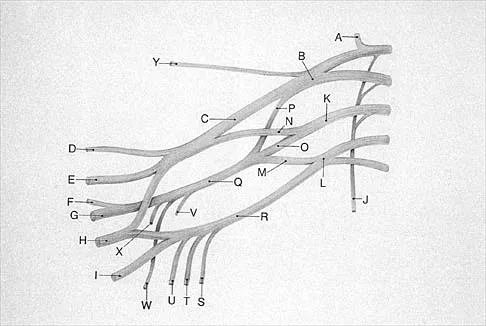

What structure is marked Q in the diagram of the brachial plexus shown in Figure 22?

Explanation